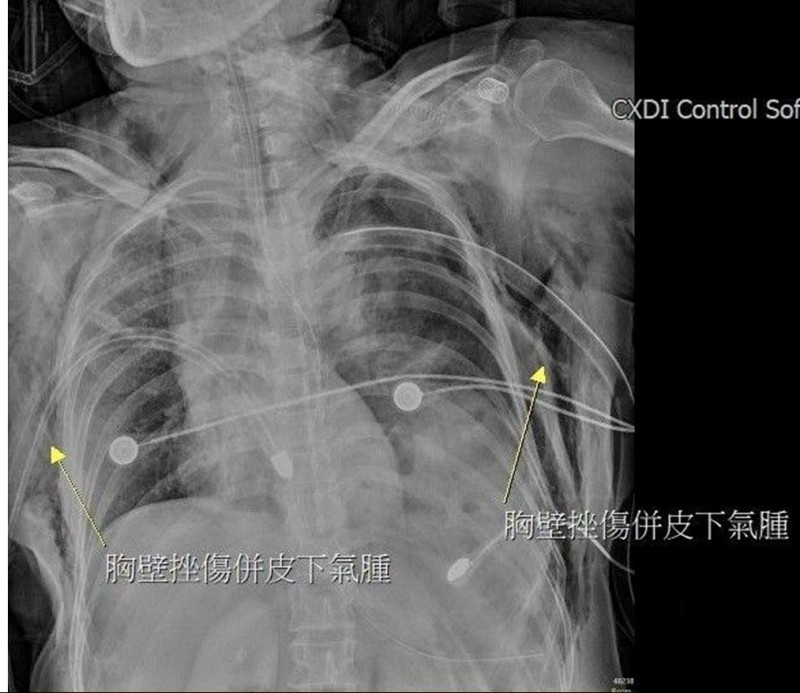

大千醫院指出,陳女被送抵急診時,出現嚴重的雙側氣胸與皮下氣腫,呼吸極度困難。經全身電腦斷層掃描發現,強大的撞擊力導致她的左側橫隔膜破裂,原本應在腹腔的胃部及部分腸道,竟位移進入左側胸腔,嚴重壓迫左肺,導致肺部無法擴張。此外,檢查更發現其下腹部大量出血(腸繫膜血管破裂)、左腳踝骨折,背部還有大面積的2至3度擦燙傷,傷勢遍布全身。